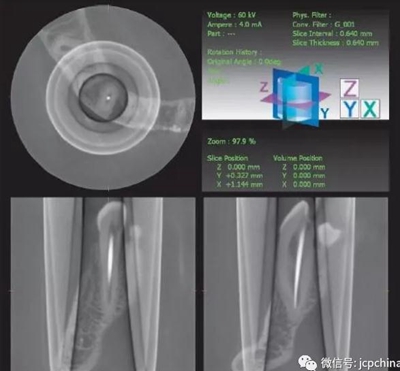

(3)部分容積效應(yīng)產(chǎn)生的偽影

如果探測器中一個(gè)高對比度物體的體積小于體素尺寸,則該對象將會(huì)有效地填充入整個(gè)體素,使其看起來比實(shí)際物體大。牙膠周邊碎片的顯影就是其中一個(gè)很好的例子,如果牙膠周邊碎片的體積小于體素大小,則圖像上會(huì)看起來比實(shí)際的大。